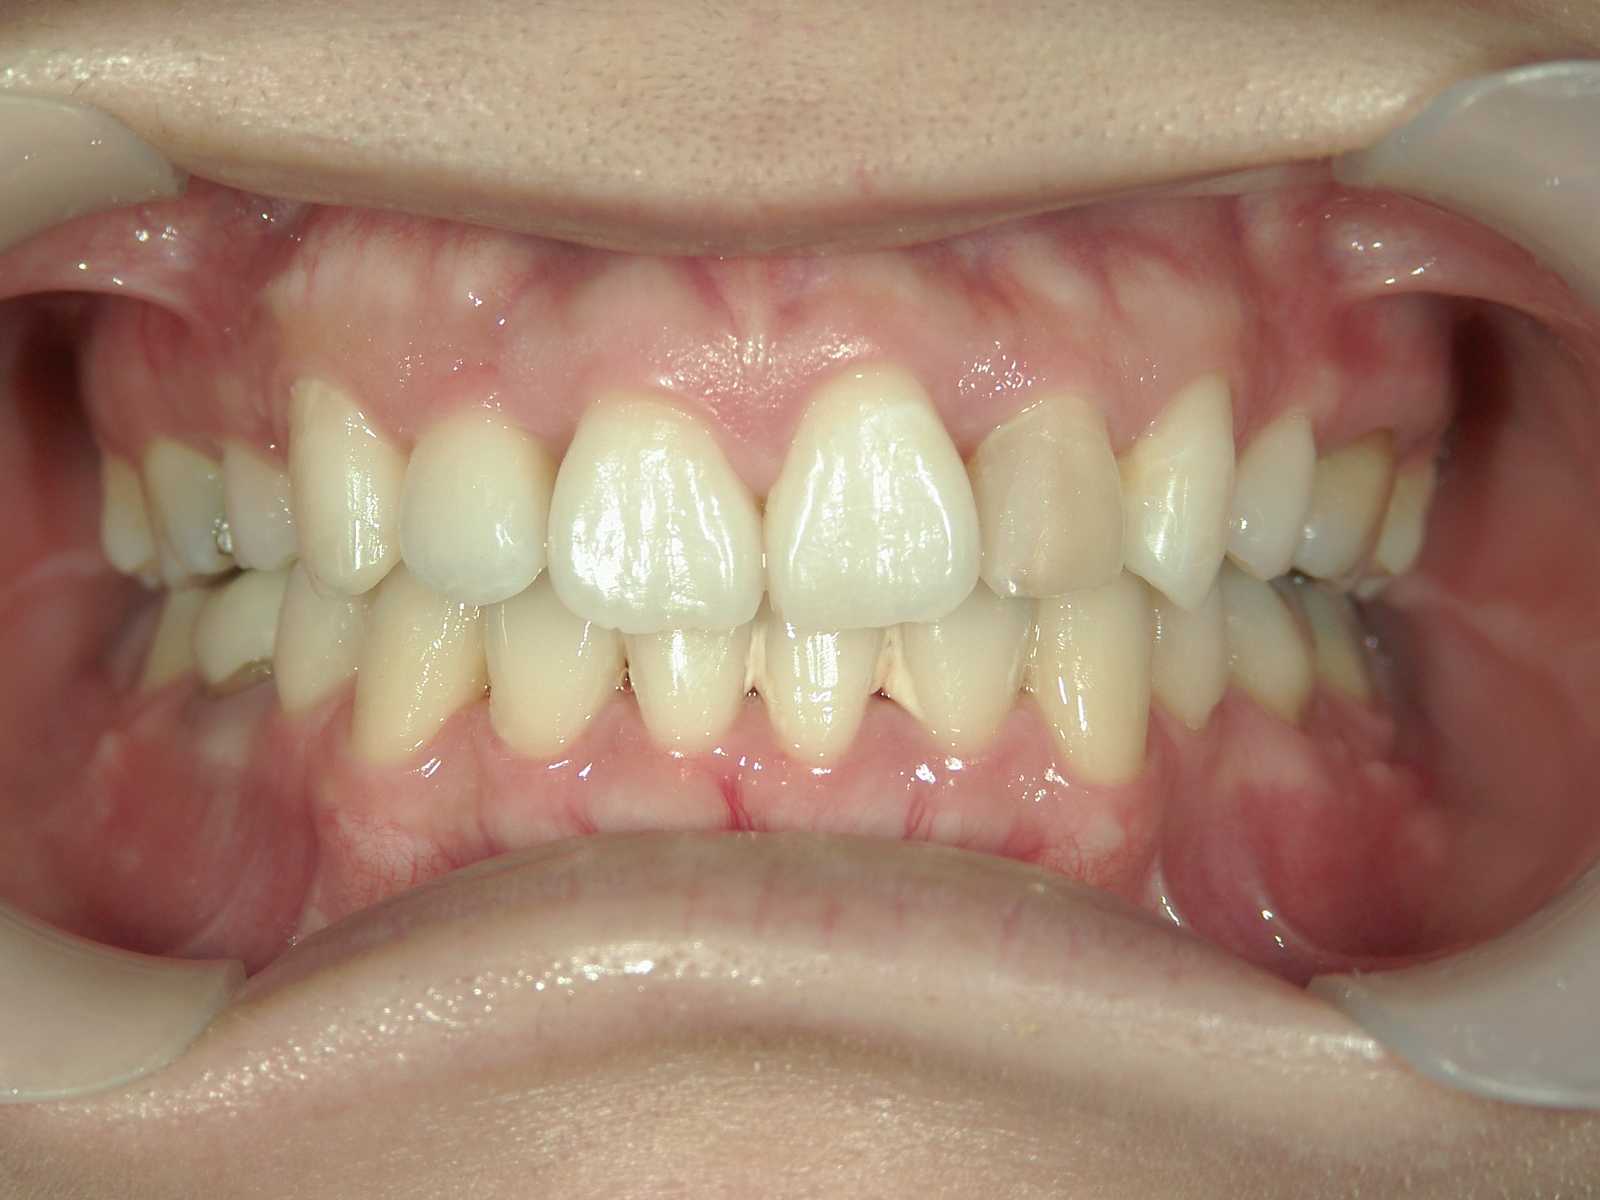

舌側ワイヤー矯正 症例(25)

主訴: 歯並びが気になる

カテゴリー : ガタガタ(叢生)